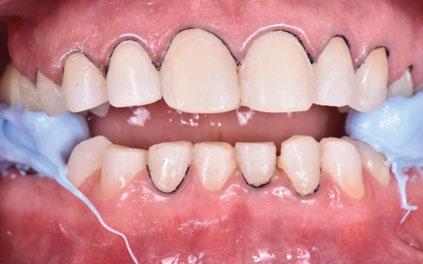

Acude a la consulta un paciente masculino de 35 años exigiendo cambios en la estética de sus dientes. El examen intraoral clínico y fotográfico reveló pérdida de estructura dentaria con facetas de desgaste en dientes anterosuperiores e inferiores, acentuándose hacia zonas oclusales de dientes posteriores.

El diagnóstico evidenció que el paciente presentaba alteración en la dinámica de la guía anterior por el desgaste de los bordes incisales, con pérdida de dimensión vertical oclusal (VDO), alteración del plano de oclusión y relaciones interoclusales inestables (Figuras 1 y 2)

Se obtuvieron modelos de estudio (Figuras 3-6) digitales mediante un escáner confocal de luz azul estructurada (PrimeScan, Dentsply Sirona) y se planificó un protocolo de desgaste mínimamente necesario y conservador de las estructuras

Figura 1. Caso inicial. Figura 2. Vista oclusal superior.